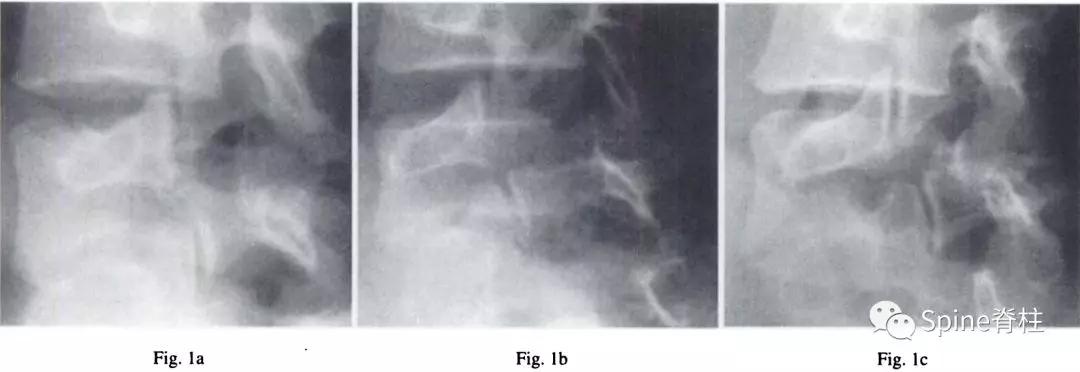

图:17岁男孩,因“腰痛伴右下肢放射痛6个月”就诊

MRI提示腰5-骶1椎间盘突出

青少年与成人LDH都可出现腰腿痛,但 青少年LDH症状通常较轻,神经功能损害(如感觉障碍、肌力下降等)较少见 ,而直腿抬高试验阳性率则可高达90%,而且常呈强阳性,多限于<30°范围。

与成人LDH相比, 青少年LDH患者出现腰椎畸形的比例较高,常见腰部僵硬、脊柱侧凸或旋转,常凸向患侧 ,这种畸形通常是由于疼痛而产生的代偿性脊柱侧凸。